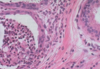

Epithelial hyperplasia (fibrocystic change)

Atypical epithelial hyperplasia (fibrocystic change)

Atypical epithelial hyperplasia (fibrocystic change)